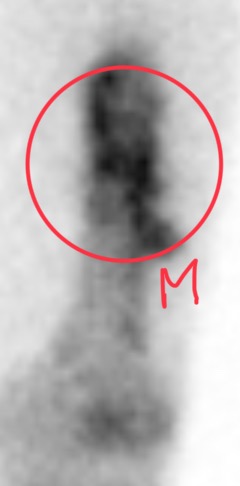

위 사진 속 M은 아주 위험한 사실을 말해주는 것였다.

전이암 재발!

재발한 뼈전이암이 무럭무럭 자라고 있다는 사실!

위 사진을 보면, 확대, 더 큼직하다.

저 정도로 진행되고 있다는 건 무서운 일이었다.